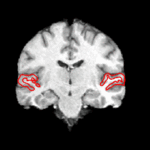

DTI-based SegmentationUnlike conventional MRI, DTI provides adequate contrast to segment the thalamic nuclei, which are gray matter structures. More... | |